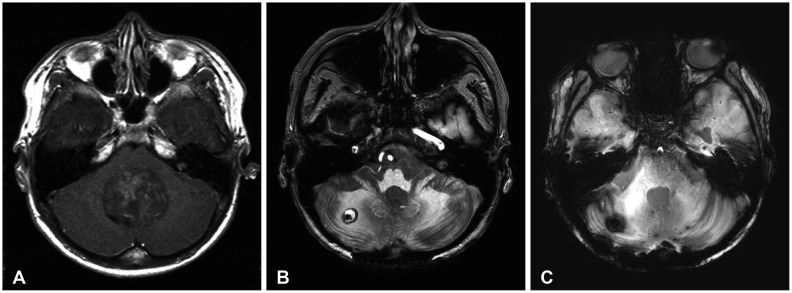

辐射诱发海绵体畸形(RICMs)是高剂量放射治疗的罕见但重要的晚期并发症,特别是在年轻的脑肿瘤幸存者中。本报告报告了两例经积极多模式治疗的RICMs,包括手术、化疗和放疗。病例1是一名22岁男性髓母细胞瘤患者,接受颅脊髓照射、肿瘤床增强和串联自体外周血干细胞移植治疗。治疗完成约8年后,常规随访影像学显示右侧小脑局灶性小出血,符合RICM。该病变无症状,采用常规影像学保守治疗,随着时间的推移显示自发消退,治疗后9年显著缩小。病例2描述了一名32岁男性颅内生殖细胞瘤接受全心室照射治疗。治疗三年后,患者在已存在的发育性静脉异常附近出现了症状性出血性RICM。手术切除和伽玛刀手术稳定病变;然而,残余症状,包括震颤和步态障碍,持续存在,影响患者的日常活动。这些病例说明了RICMs的不同临床过程,从自发消退到手术干预的必要性,并强调了长期监测和针对晚发性并发症的量身定制管理策略的重要性。

Radiation-induced cavernous malformations (RICMs) are rare but significant late complications of high-dose radiation therapy, particularly in young survivors of brain tumors. This report presents two cases of RICMs following aggressive multimodal treatment, including surgery, chemotherapy, and radiation therapy. Case 1 was a 22-year-old male patient with medulloblastoma treated with craniospinal irradiation, tumor bed boost, and tandem autologous peripheral blood stem cell transplantation. Approximately 8 years after treatment completion, routine follow-up imaging revealed a small focal hemorrhage in the right cerebellum, consistent with an RICM. The lesion was asymptomatic and managed conservatively with regular imaging, showing spontaneous resolution over time, with a significant size reduction noted 9 years post-treatment. Case 2 describes a 32-year-old male with an intracranial germinoma treated with whole-ventricular irradiation. Three years after treatment, the patient developed a symptomatic hemorrhagic RICM near a pre-existing developmental venous anomaly. Surgical resection and Gamma Knife Surgery stabilized the lesion; however, residual symptoms, including tremors and gait disturbances, persisted, affecting the patient's daily activities. These cases illustrate the diverse clinical courses of RICMs, ranging from spontaneous resolution to the necessity of surgical intervention, and emphasize the importance of long-term surveillance and tailored management strategies for late-onset complications.